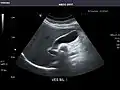

Kidneys: Right and left kidneys measure 11.5 cm and 12 cm in length respectively. No hydronephrosis. Small left lower pole kidney cyst.

Right kidney -